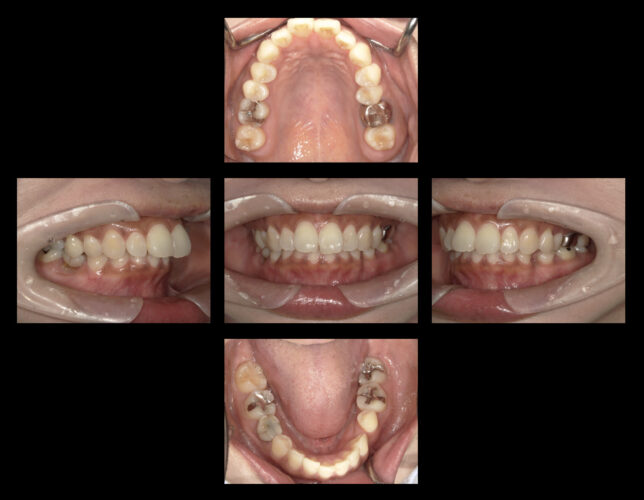

初診時

矯正後